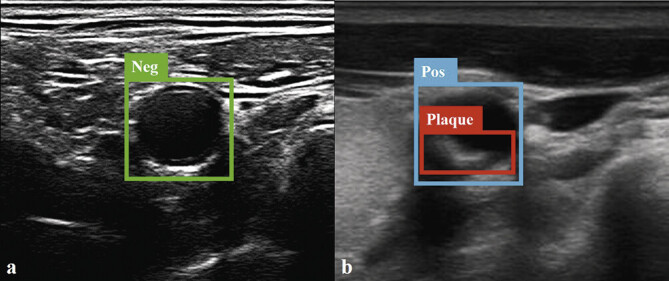

Purpose: Carotid ultrasound allows noninvasive assessment of vascular anatomy and function with real-time display. Based on the transfer learning method, a series of research results have been obtained on the optimal image recognition and analysis of static images. However, for carotid plaque recognition, there are high requirements for self-developed algorithms in real-time ultrasound detection. This study aims to establish an automatic recognition system, Be Easy to Use (BETU), for the real-time and synchronous diagnosis of carotid plaque from ultrasound videos based on an artificial neural network.

Materials and methods: 445 participants (mean age, 54.6±7.8 years; 227 men) were evaluated. Radiologists labeled a total of 3259 segmented ultrasound images from 445 videos with the diagnosis of carotid plaque, 2725 images were collected as a training dataset, and 554 images as a testing dataset. The automatic plaque recognition system BETU was established based on an artificial neural network, and remote application on a 5G environment was performed to test its diagnostic performance.